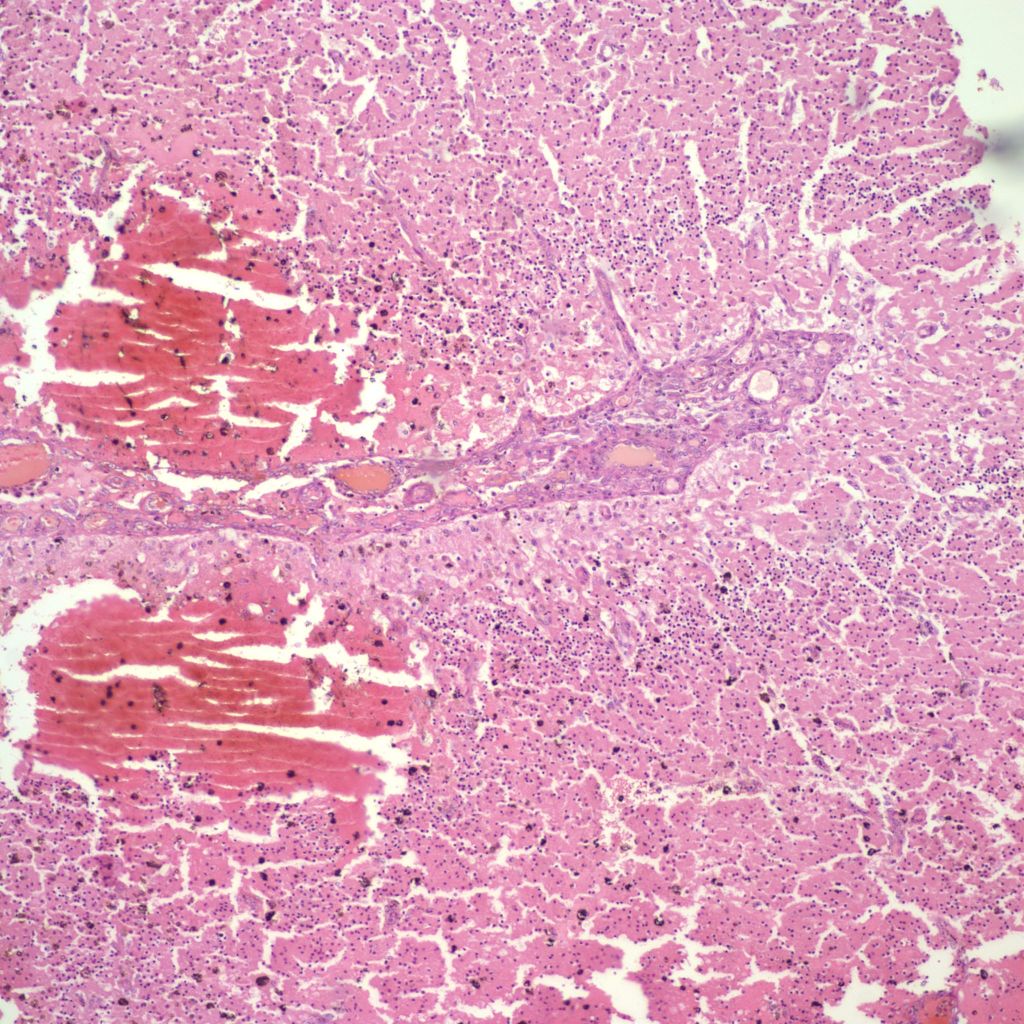

A simple grading system for IVH is: Grade 1: hemorrhage confined to the germinal matrix; Grade 2 hemorrhage into but not expanding the ventricle; Grade3 hemorrhage expanding the ventricle; Grade 4 hemorrhage into the white matter. Since the blood is likely to follow the path of least resistance, these Grade 4 hemorrhages likely flow into areas of periventricular leukomalacia which are also more frequent in more premature infants (Fig 3).